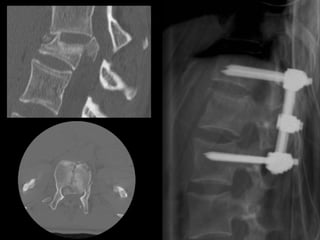

FUSION FOR LOWBACK PAIN Noninstrumented fusion

FUSION FOR LOWBACK PAIN Interbody fusion

remove the disc Interbody fusion • removethe pain source • stop the movement FUSION FOR LOW BACK PAIN

benefits Anterior interbody • anterior muscle-splitting only • minimal tissuetrauma indications • isolated degeneration • L5-S1 (L4-5) • no need to enter canal • thin, no previous major abdominal surgery FUSION FOR LOW BACK PAIN

benefits Transforaminal interbody • allows nerve decompression • allows alllevels • familiarity indications • not suitable for ALIF • nerve compression esp foraminal compression • correction of deformity